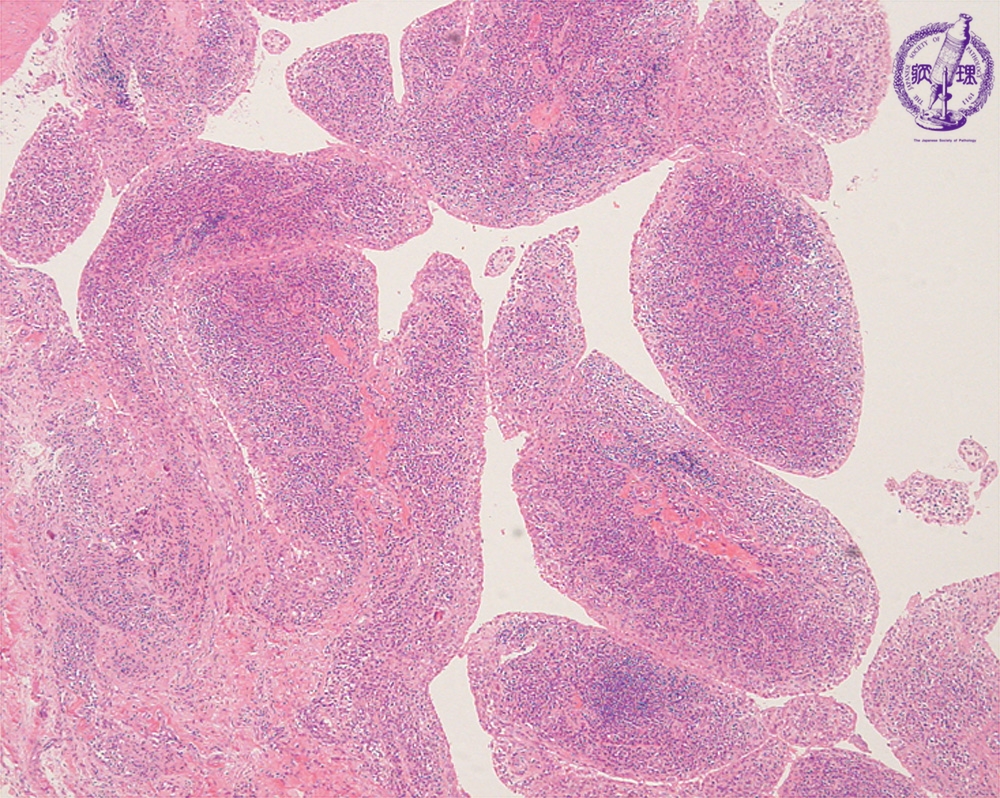

- ★(2)Rheumatoid arthritis

Microscopic view (HE; low power view): Chronic active inflammation of synovium: Villous proliferation and inflammatory cell infiltration with lymphoid follicles are seen.Compare to normal synovial tissue.